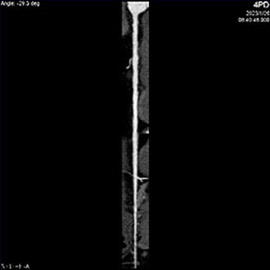

80列マルチスライスCTで撮影した画像

心臓(冠動脈)

主に狭心症や心筋梗塞などの診断